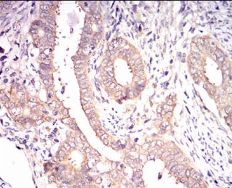

| AC2132 | EIF2A Mouse Monoclonal antibody[3A7A8] | 100ug | $367 | 10days |

| AC2132 | EIF2A Mouse Monoclonal antibody[3A7A8] | 200ug | $660.6 | 10days |